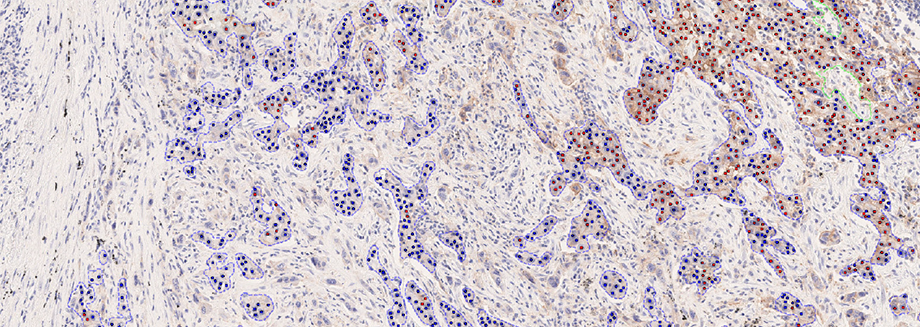

Hørsholm, Denmark — Visiopharm A/S, an innovator in AI-powered digital pathology solutions, has announced the IVDR certification of its PD-L1 APP for non-small cell lung cancer (NSCLC). The APP provides fully automated evaluation for the predictive biomarker, offering whole slide analysis results to the pathologist with no prior interaction needed. With exceptional accuracy and consistency in biomarker scoring related to eligibility for immune checkpoint inhibitors, it integrates seamlessly with PACS/IMS systems used by pathology labs, ensuring optimal workflow efficiency.

Achieving IVDR requires a significant effort, and the PD-L1 APP is the 9th IVDR clearance for Visiopharm. The validation is based on the results of a comprehensive clinical study encompassing a large patient cohort and evaluations from three distinct European sites. The study directly compared manual assessments with the APP’s stand-alone analysis and APP-assisted interpretations. The results were remarkable, demonstrating substantial to near-perfect agreement with the multi-reader reference score and a high concordance with gold-standard expert manual assessments. Most notably, the data indicates increased agreement rates with pathologists reporting efficiency gains when using the APP, underpinning the fully automated APP’s potential to address the primary challenges of PD-L1 IHC scoring.